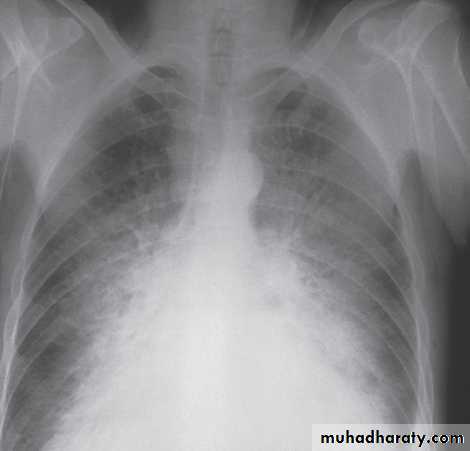

Chest X-ray - cardiac size enlarged and evidence of pulmonary congestion .